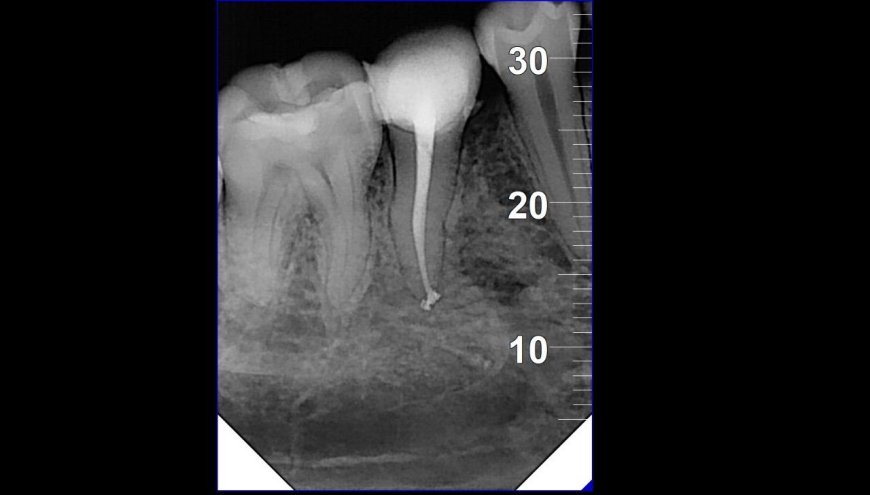

18 الدكتور احمد حسان | أفضل دكتور أسنان في الاردن